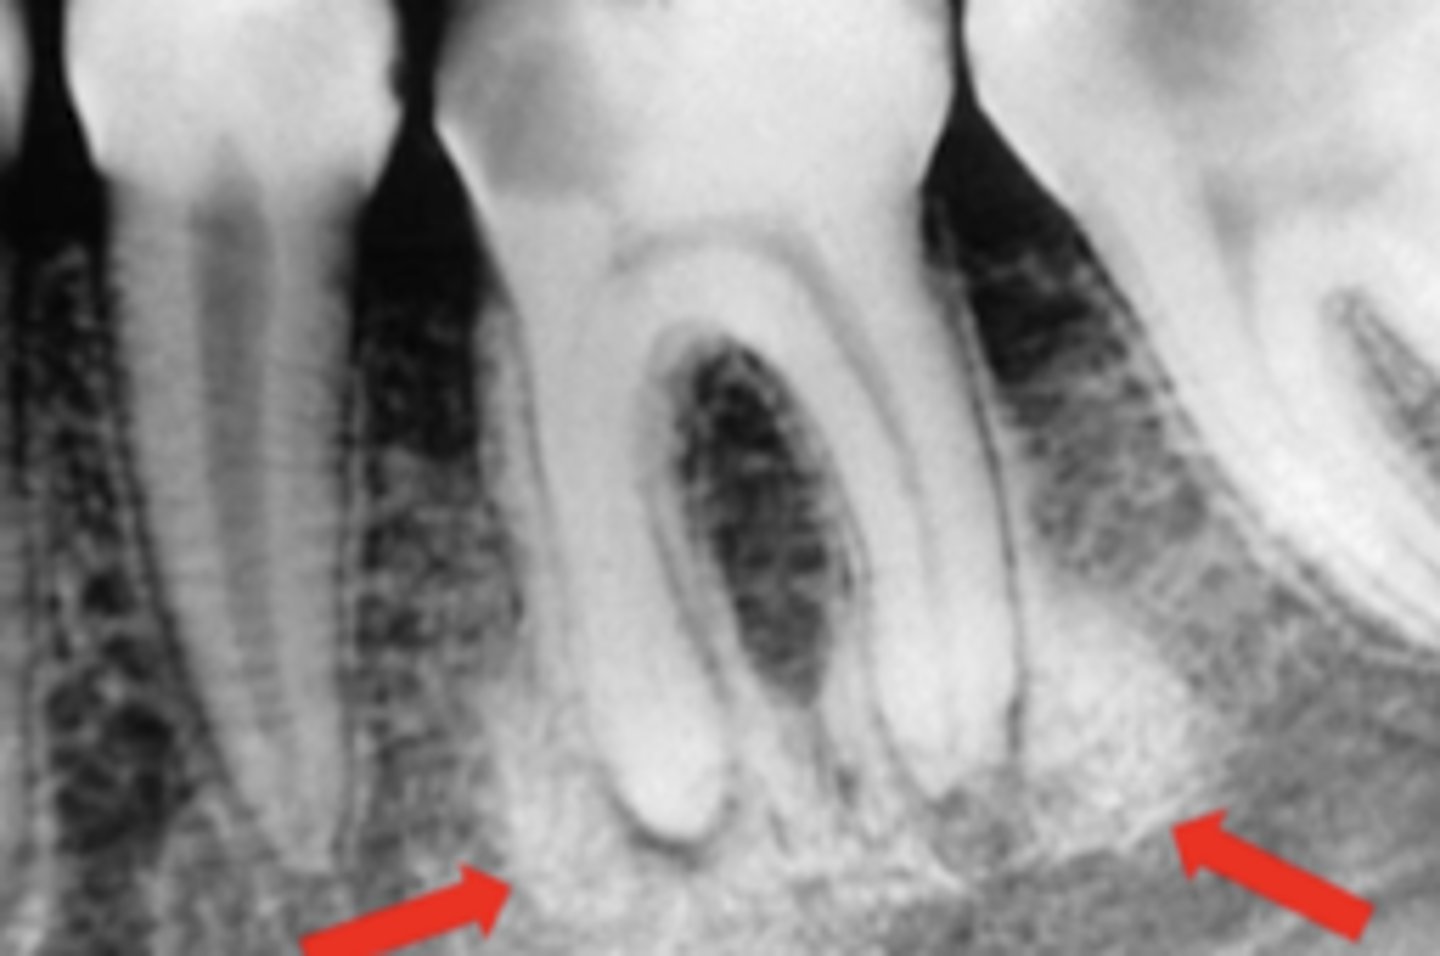

What is Periapical Rarefying Osteitis also known as?

Granuloma

What kind of teeth are affected by Periapical Rarefying Osteitis?

Nonvital teeth

What indicates chronic inflammation in Periapical Rarefying Osteitis?

Sequel of an acute episode